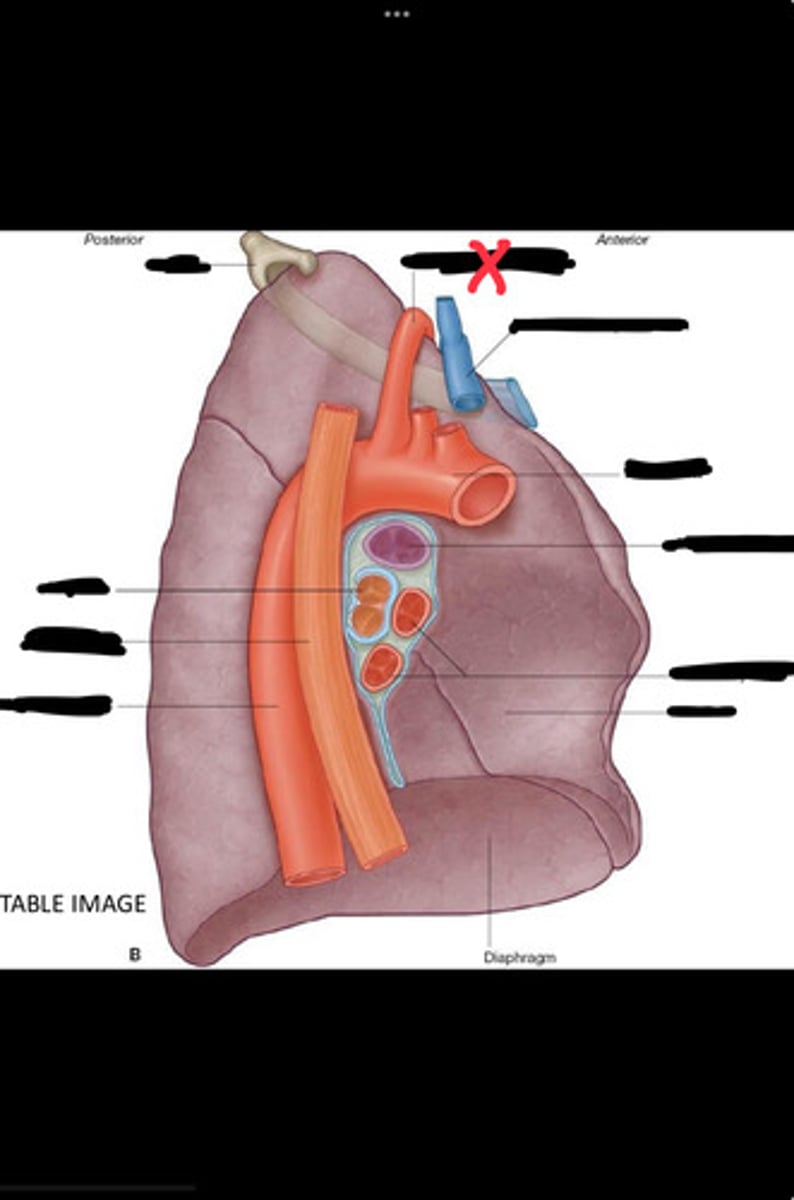

Diaphragm

Inferior vena cava

Superior vena cava

Subclavian vein

Right bracheocephalic vein

Subclavian artery

Esophagus

Bronchus

Rib 1

Left subclavian artery

Left brachiocephalic vein

Aortic arch

Pulmonary artery

Pulmonary vein

Heart

Left brachiocephalic vein

Azygos vein

Esophagus

Bronchus

Fibrous pericardium

Parietal layer of serous pericardium

Pericardial cavity

Visceral layer of serous pericardium

Junction between fibrous pericardium and adventitia

Heart

Thoracic aorta

Rib 1

Pulmonary artery

Bronchus to superior lobe